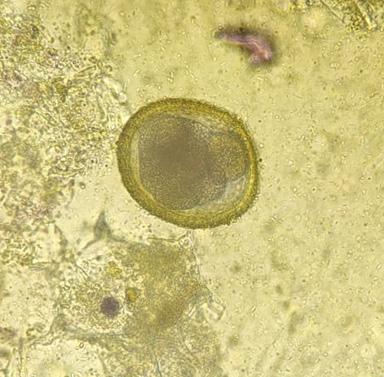

Prevalencia de parasitosis entéricas transmisibles de perros domésticos a humanos en la ciudad de La Paz, Bolivia

Prevalence of enteric parasitosis transmissible from domestic dogs to humans in La Paz city, Bolivia

Camila Isabel Palma Tovar, Marisol Colquehuanca Vino, Helen Condori Canaviri, Gina Gabriela López Blanco, Grisel Mireya Mamani Tuco, Carla Irene Paricollo Ancasi, Damaris Lindsay Quisbert Bautista, Valery Nayely Silva Molina..............................................................43-50